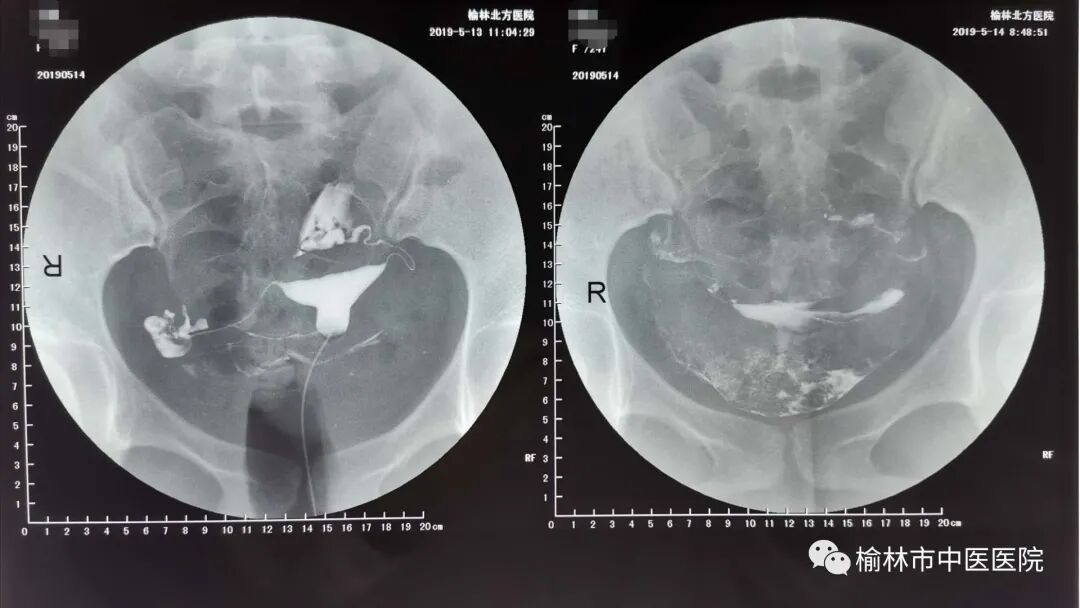

子宫输卵管碘化油造影术

子宫输卵管造影( hysterosalpingography,HSG)是通过导管向宫腔及输卵管注入造影剂,行X线透视及摄片,根据造影剂在输卵管及盆腔内的显影情况了解输卵管是否通畅、阻塞部位及宫腔形态。该检查损伤小,能对输卵管阻塞作出较正确诊断,准确率可达80%,且具有一定的治疗功效。